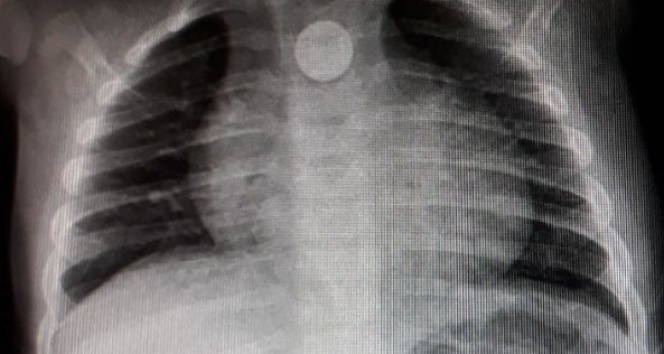

Bozuk para röntgen filminde ortaya çıktı

Yoğun bakıma alınan minik bebeğe önce film çekildi. 9 aylık Mustafa'nın boğazına takılan madeni para filmde ortaya çıkınca doktorlar tarafından operasyon yapıldı. Boğazındaki 1 lira çıkarılan minik bebek daha sonra rahat nefes almaya başladı. 1 gün hastanede müşahade altında tutulan küçük çocuk bugün taburcu edildi. Doktorların zamanında müdahalesiyle yeniden hayata dönen küçük çocuğu evinde yeniden oyuncaklarıyla oynamaya başlaması ev sakinlerini sevindirdi.